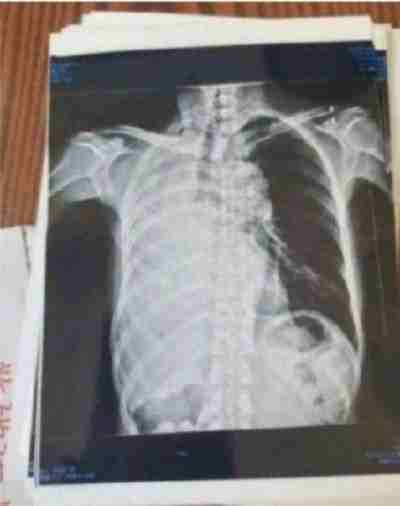

案例 1:食道癌患者

这是治疗前:病变长约7cm。从吃饭困难到滴水不进。

2023年10月9日在山西肿瘤检查:病变长度7cm。从2023年10月28月开始服用中药;2024年3月24日拿中药:2024年8月29日山西肿瘤医院复查(病变7cm癌变消失)。目前:吃饭一大碗,一切很好,参加农业劳动。这是一位贫困山村的农妇。

食道癌患者从吃饭困难到滴水不进。经两次治疗:7公分的食道癌经省肿瘤医院CT检查:病灶消失。至今每顿一大碗,馍头,面条。米饭都能,并时常参加农业劳动!两个月临床治愈!患者送上锦旗以表对陈海林医生的感谢